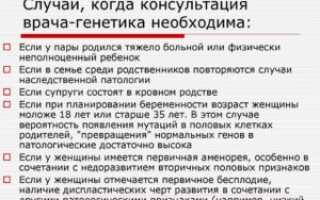

Консультация генетика при беременности Наследственность играет немаловажную роль в жизни каждого человека. Благодаря ей мы берём от наших родителей черты...